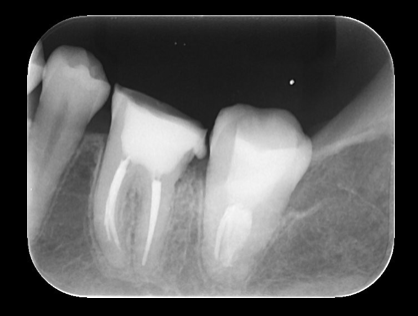

根管治療後のデンタルX線写真